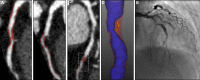

Background: The future risk of myocardial infarction is commonly assessed using cardiovascular risk scores, coronary artery calcium score, or coronary artery stenosis severity. We assessed whether noncalcified low-attenuation plaque burden on coronary CT angiography (CCTA) might be a better predictor of the future risk of myocardial infarction.

Methods: In a post hoc analysis of a multicenter randomized controlled trial of CCTA in patients with stable chest pain, we investigated the association between the future risk of fatal or nonfatal myocardial infarction and low-attenuation plaque burden (% plaque to vessel volume), cardiovascular risk score, coronary artery calcium score or obstructive coronary artery stenoses.

Results: In 1769 patients (56% male; 58±10 years) followed up for a median 4.7 (interquartile interval, 4.0-5.7) years, low-attenuation plaque burden correlated weakly with cardiovascular risk score (r=0.34; P<0.001), strongly with coronary artery calcium score (r=0.62; P<0.001), and very strongly with the severity of luminal coronary stenosis (area stenosis, r=0.83; P<0.001). Low-attenuation plaque burden (7.5% [4.8-9.2] versus 4.1% [0-6.8]; P<0.001), coronary artery calcium score (336 [62-1064] versus 19 [0-217] Agatston units; P<0.001), and the presence of obstructive coronary artery disease (54% versus 25%; P<0.001) were all higher in the 41 patients who had fatal or nonfatal myocardial infarction. Low-attenuation plaque burden was the strongest predictor of myocardial infarction (adjusted hazard ratio, 1.60 (95% CI, 1.10-2.34) per doubling; P=0.014), irrespective of cardiovascular risk score, coronary artery calcium score, or coronary artery area stenosis. Patients with low-attenuation plaque burden greater than 4% were nearly 5 times more likely to have subsequent myocardial infarction (hazard ratio, 4.65; 95% CI, 2.06-10.5; P<0.001).

Conclusions: In patients presenting with stable chest pain, low-attenuation plaque burden is the strongest predictor of fatal or nonfatal myocardial infarction. These findings challenge the current perception of the supremacy of current classical risk predictors for myocardial infarction, including stenosis severity. Registration: URL: https://www.clinicaltrials.gov; Unique identifier: NCT01149590.